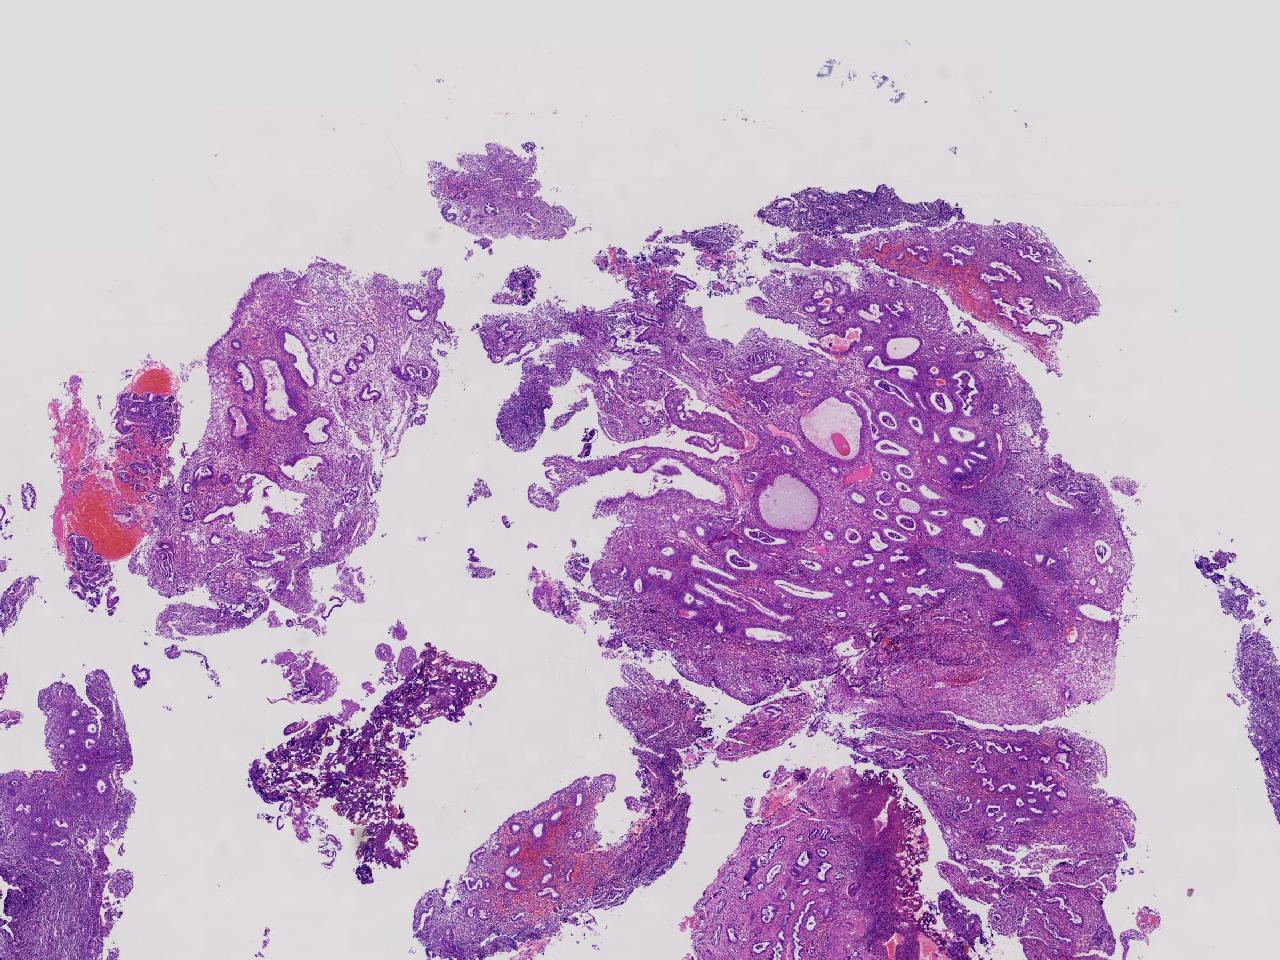

性别

女

年龄

55岁

女,55岁,月经紊乱4年,彩超示:子宫内膜增厚(内膜厚15.7mm),末次月经:2025年7月27日。

标本名称

宫腔镜下子宫内膜活检

大体所见

灰粉色不整形软组织多块,1.5X0.8X0.6厘米。

考虑:子宫内膜增生伴子宫内膜炎

子宫内膜增生紊乱,内膜息肉样结构